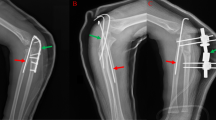

In Group B, there were 28 cases of chronic Monteggia fracture, with an average age of 7.68 ± 2.9 years (range: 1–14 years) and an average follow-up duration of 17.82 ± 10.50 months. Anterior dislocation of the radial head was observed in 24 cases, anterolateral dislocation in 3 cases, and posterolateral dislocation in 1 case. Twenty-one children underwent debridement of the humeroradial joint cavity, followed by ulna osteotomy and lengthening with plate internal fixation. Seven children received the same procedure, along with Kirschner wire fixation (typical case presented in Figs. 3 and 4). The average inner-epiphyseal ulna-radius length ratio was 1.070 ± 0.027. The average Mayo Elbow Performance Score (MEPS) at the last follow-up was 87.32 ± 7.26, the average pronation range was 71.61 ± 12.84, the average supination range was 77.14 ± 5.52, and the average flexion and extension range was 124.39 ± 12.32. All patients achieved excellent radial head reduction. Outcome parameters for both groups are summarized in Table 1.

A case of a 11-year-old boy who sustained a Bado type I Monteggia fracture at the age of 6. The patient underwent ulna osteotomy and plate internal fixation, Kirschner wire fixation, and annular ligament repair as part of preoperative diagnosis. However, post-surgery recovery did not restore inner-epiphysis ulna-radius length ratio to 1.047–1.141.

A case of a 12-year-old boy who sustained a Bado type I Monteggia fracture at the age of 10. The patient underwent ulna osteotomy, plate lengthening. The inner-epiphysis ulna-radius length ratio was restored to 1.047–1.141, the patient has an excellent recovery of elbow joint function at the 24-month follow-up.